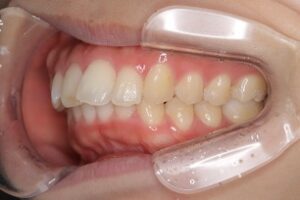

患者さんは、上下の前歯が強く突出しており、横顔を気にして来院されました。

診断の結果、口唇突出を伴う上下顎前突(skeletal2)

治療内容:

上顎左右第一小臼歯、下顎両側第二小臼歯(計4本)を抜歯

上裏側、下表側のブラケット装置で治療

治療期間は2年11ヶ月

治療中写真

結果:

口元の突出感が大きく改善